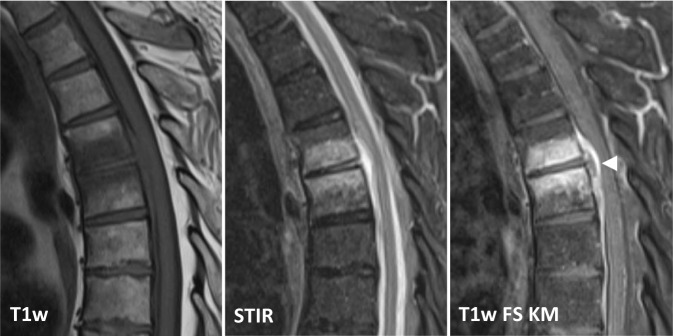

Die MRT ist mit einer Sensitivität von 96 %, einer Spezifität von 92 % und einer Genauigkeit von 94 % die Bildgebung der Wahl [4]. Noch vor knöchernen Destruktionen zeigt sich eine Zunahme des Flüssigkeitssignals der betroffenen Wirbelkörper und Bandscheiben im Sinne eines T1w-hypointensen, T2w-hyperintensen Ödems sowie in den T1-gewichteten Sequenzen eine Anreicherung von i.v.-Kontrastmittel (Abb. 2). Der Verlust des sog. „nuclear cleft sign“, einer T2w-Hypointensität der zentralen Bandscheibe, die von einigen als altersabhängig physiologischer Prozess, von anderen als erster Grad der Degeneration der Bandscheibe gewertet wird, kann mit einer Spondylodiszitis einhergehen, ist für eine solche jedoch nicht spezifisch [14].

Die Entzündungsreaktion lässt sich meist zunächst anterolateral im Wirbelkörper in der Nähe der Endplatten abgrenzen und zeigt nach Kontrastmittelgabe in T1-gewichteten Sequenzen eine teilweise inhomogene Kontrastmittel-Mehranreicherung. Das assoziierte Ödem betrifft hingegen typischerweise den größten Teil des Wirbelkörpers und der angrenzenden Bandscheibe [4]. Bei der tuberkulösen Spondylodiszitis bzw. Spondylitis kann die Bandscheibe weitgehend erhalten sein, da diese häufig vorrangig den Knochen, insbesondere die dorsalen Wirbelanteile, betrifft [15].